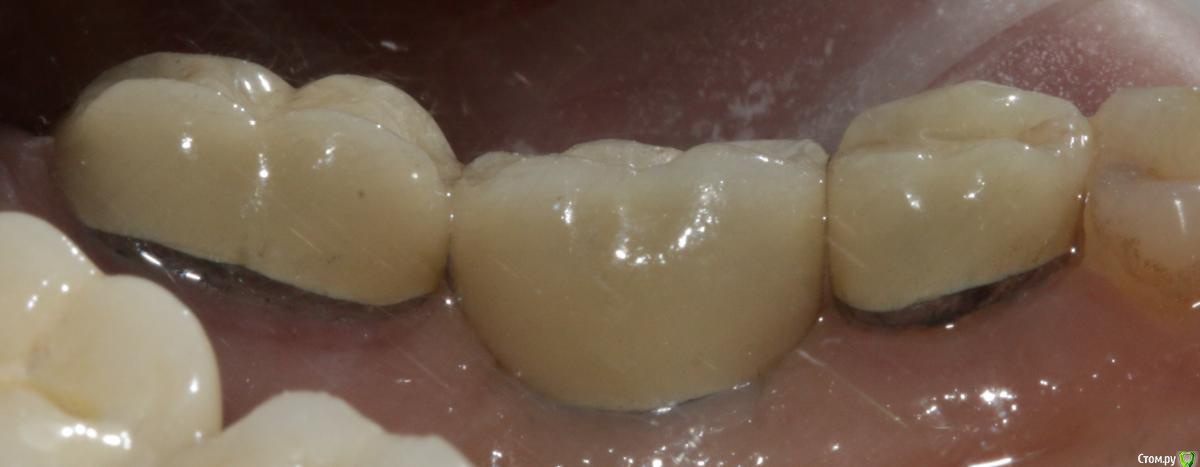

Ильдар Опубликовано 29 марта, 2015 Поделиться Опубликовано 29 марта, 2015 Коллеги, здравствуйте!Вот демонтировал старье. мк на зубы.имплант 4310, поставил поглубже.мк на имплант - техник прислал коронку с шахтой и абатмент,я склеил на fuji1. закрутил на 35 н.залепил не очень красиво , но с плавиковой, силаном и олбонд 3. думаю надежно.контрольный прицельный есть, видимо забыл его. извиняюсь за нечеткие fото. буду рад отзывам 3 Ссылка на комментарий

k.t.m. Опубликовано 29 марта, 2015 Поделиться Опубликовано 29 марта, 2015 все нра и прилегание коронок на зубах и витальность, но вот дентиум больше 1мм не стал бы заглублять,при отсроченном протоколе.и для одиночек снимаю закрытым методом-меньше возни 1 Ссылка на комментарий

Nemiroff Опубликовано 12 апреля, 2015 Поделиться Опубликовано 12 апреля, 2015 (изменено) в каталоге дентиум написано, что абатменты фиксируются усилием 25-30 ньютон. при большем усилии, если вы будете пытаться открутиться с конусной системы, то имеете высокий риск сломать винт, сорвать шахту винта или просто не открутить ничего. показаний к заглублению в данном клиническом случае нет на мой взгляд.а показания к круговой гирлянде не соседних зубах заключались в их витальности и необходимости сделать тонкий переход края коронки в тонкий уступ? Изменено 12 апреля, 2015 пользователем Nemiroff Ссылка на комментарий

Dr.Sham Опубликовано 15 апреля, 2015 Поделиться Опубликовано 15 апреля, 2015 МК вообще должна быть либо по кругу с гирляндой, либо с плечом. Ссылка на комментарий